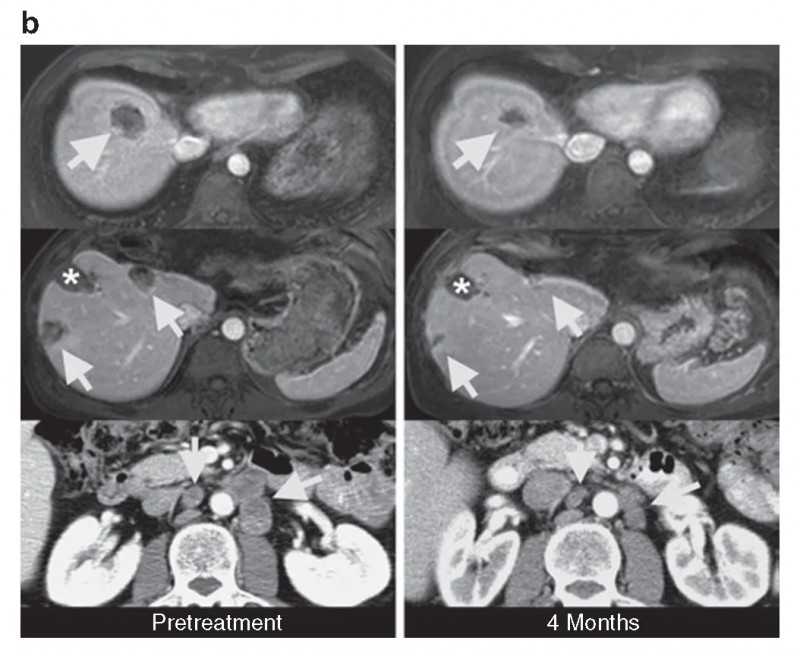

患者3在治疗3个月时,肝、肺及腹主动脉旁淋巴结转移瘤按实体瘤疗效评价标准(RECIST)缩小34%,4个月时缩小幅度达49%(详见下图),达到RECIST确认的部分缓解(PR)。

▼患者3在治疗前、治疗后4个月的计算机断层扫描(CT)图像

▲图源“Mol Ther”,版权归原作者所有,如无意中侵犯了知识产权,请联系我们删除

注:

①箭头表示:结直肠癌转移灶的位置;

②星号表示:先前接受过射频消融(RFA)治疗的肝转移灶部位的肝脏缺损。